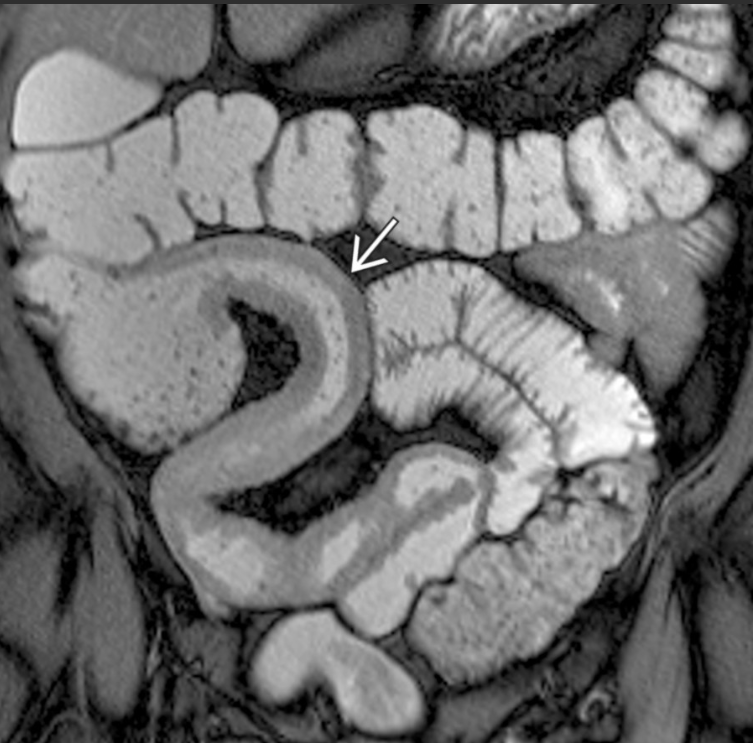

A __________ (doença de Crohn/retocolite ulcerativa) envolve todas as camadas intestinais, podendo resultar em fístulas.

A __________(doença de Crohn/retocolite ulcerativa) tem inflamação confinada à mucosa e submucosa do intestino grosso.

Doença de Crohn; retocolite ulcerativa.

Fístula entre alças de intestino delgado em paciente com Crohn; a alta resolução de partes moles da RM ajuda a delimitar melhor fístulas pequenas.